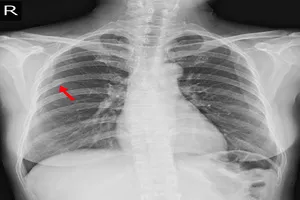

13. 폐렴

폐렴은 폐에 염증이 생겨 숨쉬기가 힘든 질환입니다. 감기에 걸렸을 때처럼 기침이 나고 가래가 끓으며, 열이 나고 가슴이 아픈 증상이 나타날 수 있습니다. 항생제를 사용하여 치료하고 충분히 쉬는 것이 중요합니다.